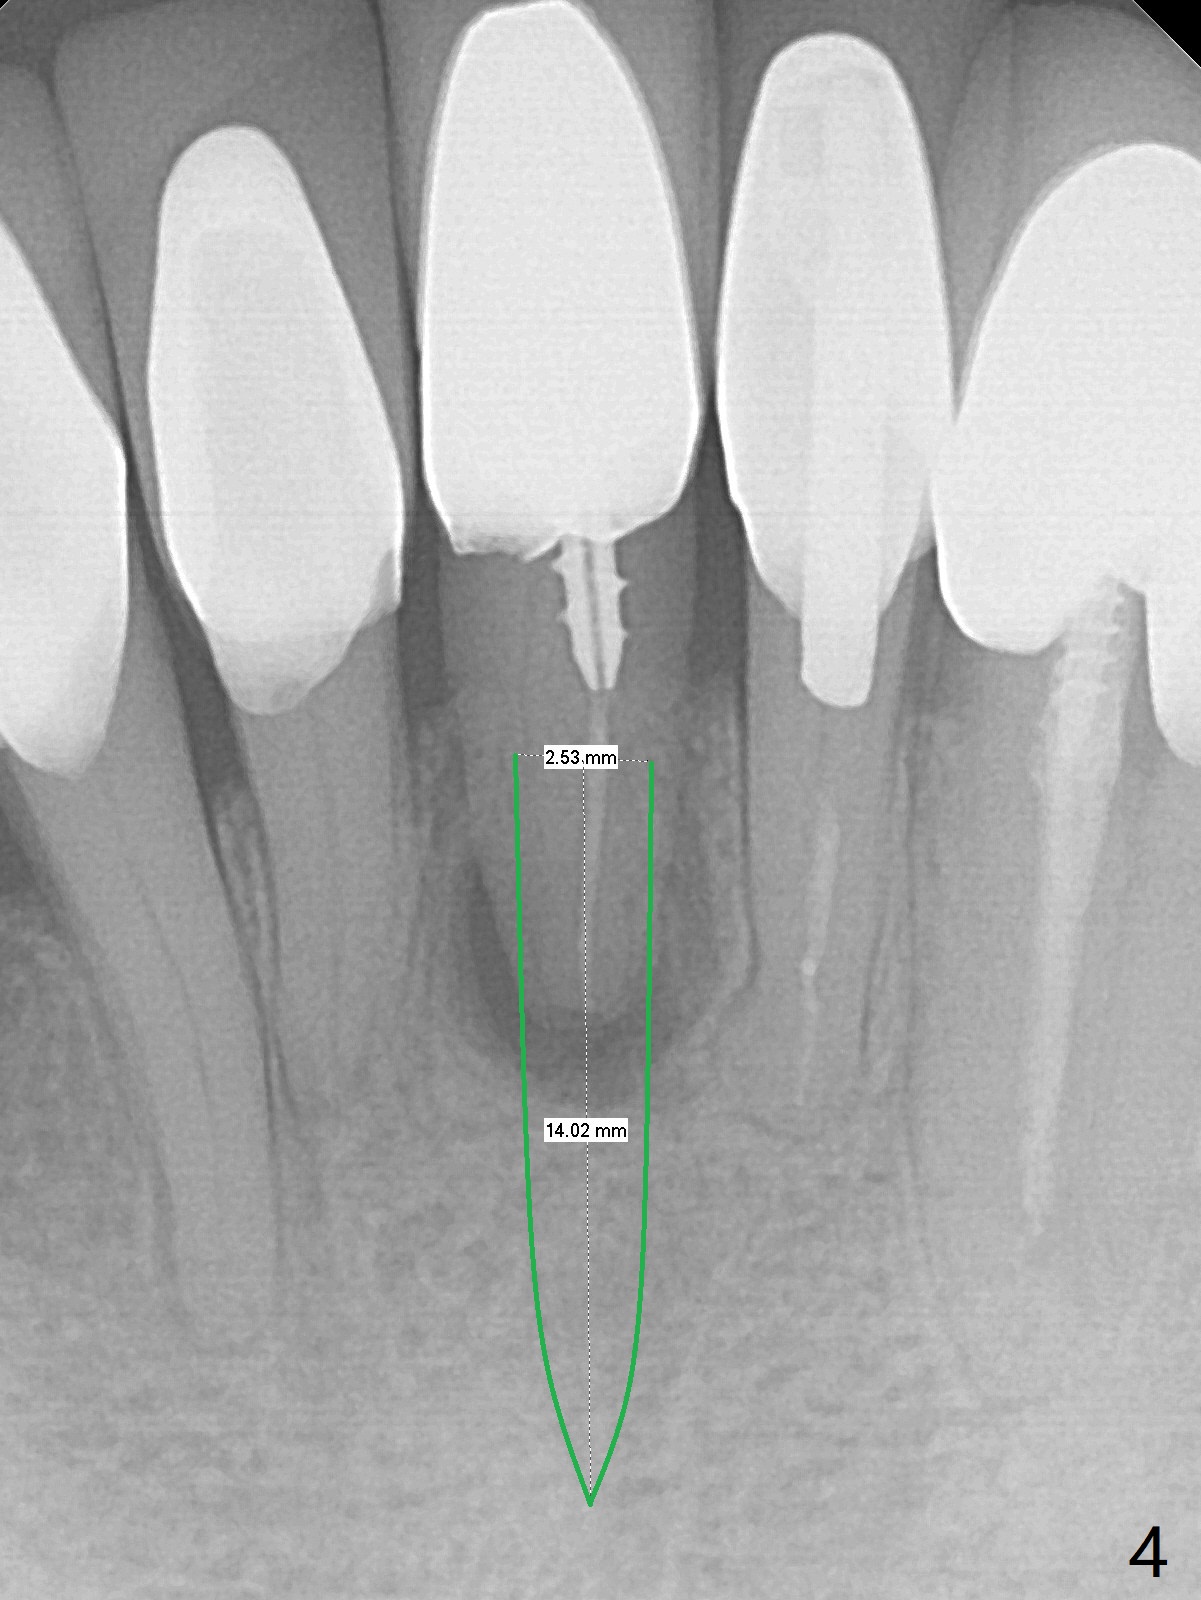

A 74-year-old man finally agrees to have the tooth #24 to be extracted for immediate implant with 3-year mobility and buccal shift (occlusal trauma or root fracture, Fig.0,1). Because of curved root tips of the neighboring teeth (Fig.1 red dashed line), the initial osteotomy will be created mesially (Fig.2 red arrow), followed by change in trajectory (Fig.3). The initial depth will be 14 mm (gingival level; ~ 12 mm bone level (easy change in trajectory and/or position). PA will be taken. The implant will be 2.5x14 mm (Fig.4).